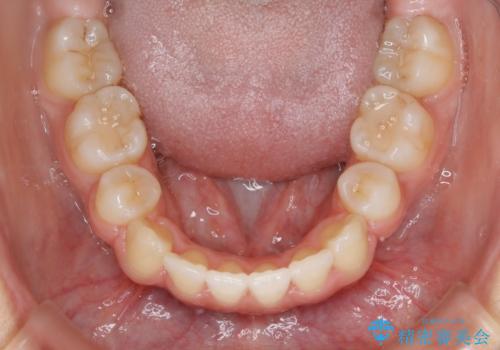

- 口元を下げたいという主訴でご来院されました。

ガタつきの度合いは軽度でしたが歯列の幅が狭く、その分前歯が上下とも前方に出てしまっていました。

しっかりと口元・顔貌まで変化を起こせるように上下左右の第一小臼歯を抜歯し、ワイヤー装置にて矯正を開始することとなりました。